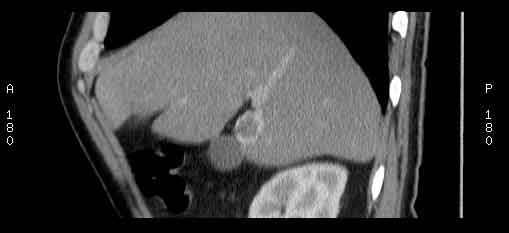

Сонограммы, КТ- артериальная, портальная и отсроченная паренхиматозная фазы

Сделали КТ (весьма похвальная тактика); по КТ: в артериальную фазу: периферическое усиление в виде сливающихся островков контраста, с центрипетальной направленностью. Венозная и отсроченная фаза-хорошее накопление контраста; образование практически изоденсно по отношению к паренхиме печени. Классика гемангиомы. Вуаля-диагноз на "тарелочке".